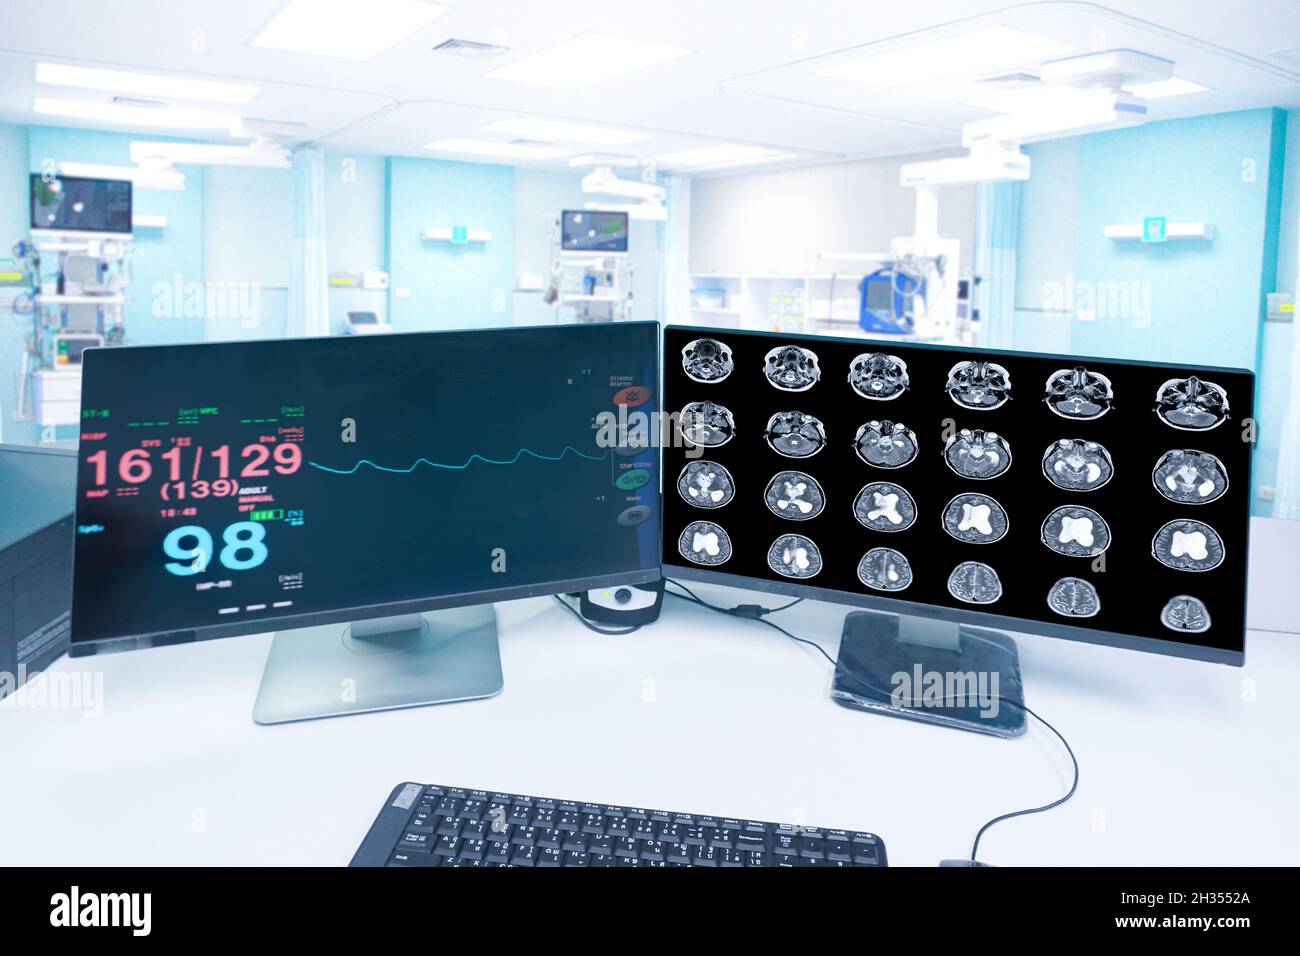

Motion blur in the emergency room hospital, a monitor showing Vital signs, and MRI brain scan , Medical healthcare concept. Stock Photohttps://www.alamy.com/image-license-details/?v=1https://www.alamy.com/motion-blur-in-the-emergency-room-hospital-a-monitor-showing-vital-signs-and-mri-brain-scan-medical-healthcare-concept-image449427282.html

Motion blur in the emergency room hospital, a monitor showing Vital signs, and MRI brain scan , Medical healthcare concept. Stock Photohttps://www.alamy.com/image-license-details/?v=1https://www.alamy.com/motion-blur-in-the-emergency-room-hospital-a-monitor-showing-vital-signs-and-mri-brain-scan-medical-healthcare-concept-image449427282.htmlRF2H3552A–Motion blur in the emergency room hospital, a monitor showing Vital signs, and MRI brain scan , Medical healthcare concept.